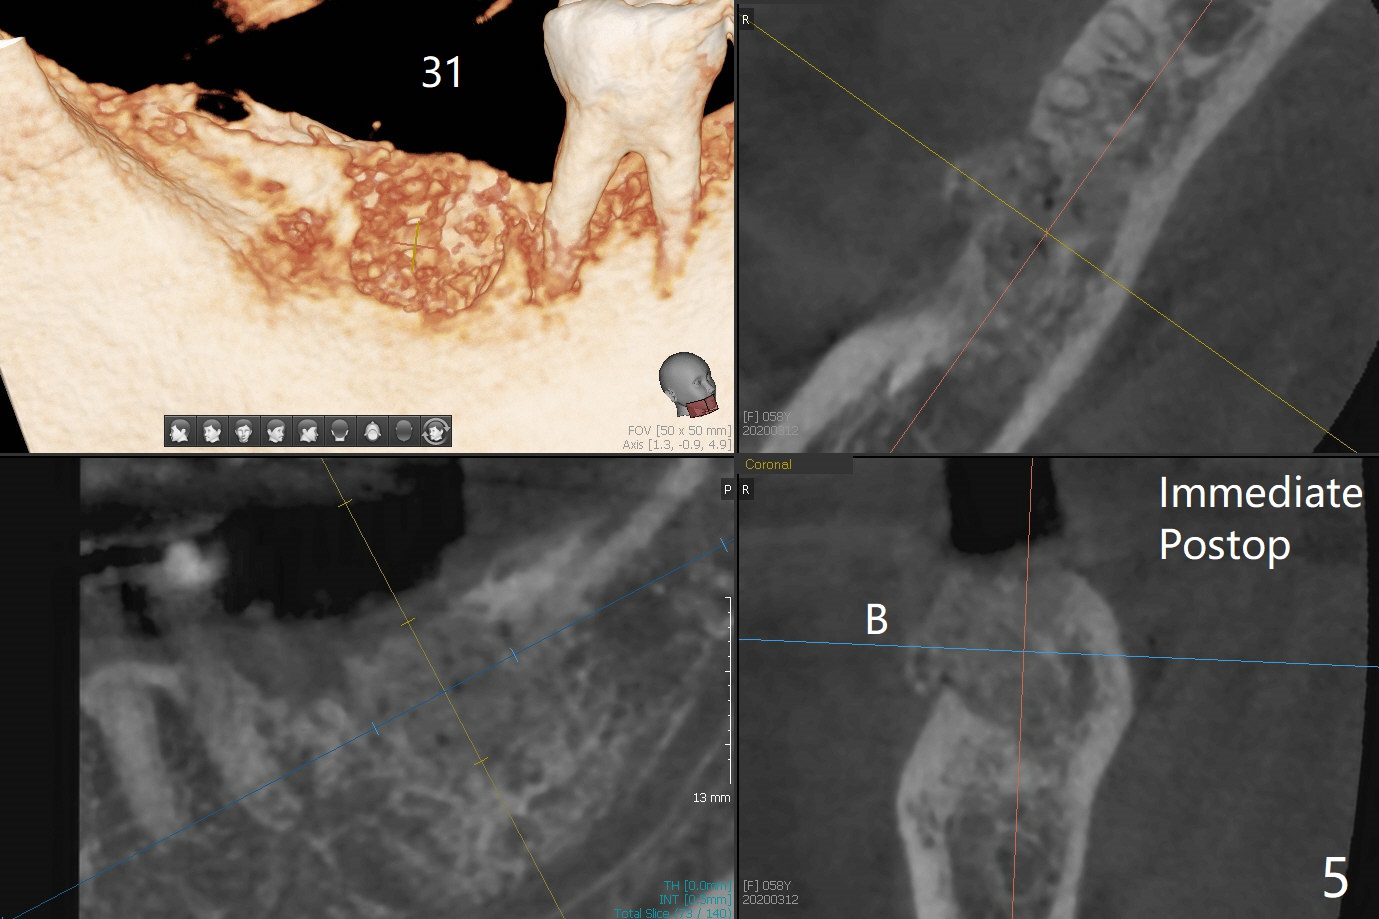

After extraction of the tooth #31 with mesial root fracture and a buccal fistula (Fig.1 <) and debride-ment, cortical: cancellous (50: 50) mineralized allograft (.5-1 mm) saturated with ~ .3 ml of .3 mg/ml of rhPDGF-BB (one component of GEM21S) is placed in the socket. Amazingly bone graft granules seem to stick to each other (semi sticky bone (Fig.2), as compared to PRF). The socket opening is covered with a piece of Osteogen plug and 12x12 mm Amnion-Chorion Allograft, followed by 4-0 PGA suture (Fig.3). The bone graft is packed as apical (Fig.4) and buccal (Fig.5 B) as possible. The patient will return to soft tissue healing check in a week. CT will be taken to determine whether the buccal plate is repaired 4 months postop. Watch Video. In fact COVIT 19 delays her return. The buccal plate seems to have reformed 7 months postop (Fig.6 >). The width and height of the ridge remains basically the same (compare Fig.7 and 8).